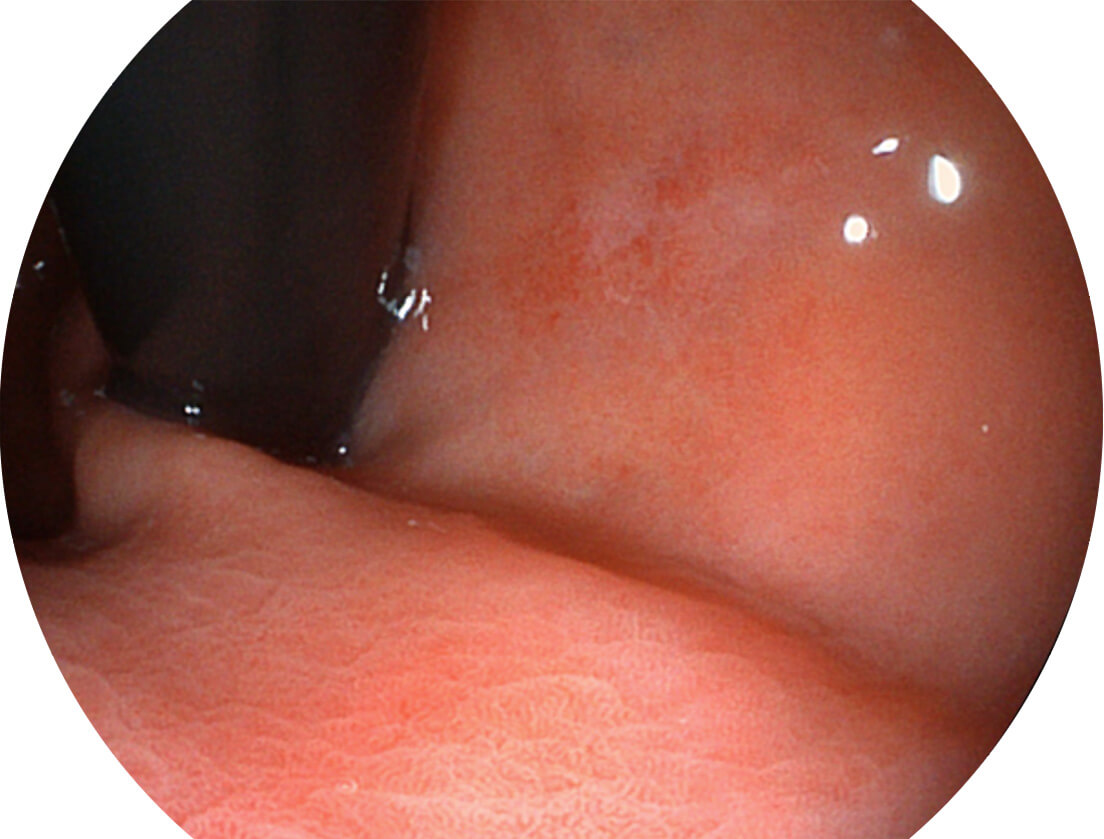

• 1080P全高清画质

采用无损耗高清数字接口,视频输出分辨率≥1920×1080,图像清晰、细腻。

• VLS-55系列四波长LED光源

采用光路合束技术,光谱自由度高,实现了更丰富的照明模式,染色模式SFI及VIST,从远景到近景,助力消化道早期疾病诊断。